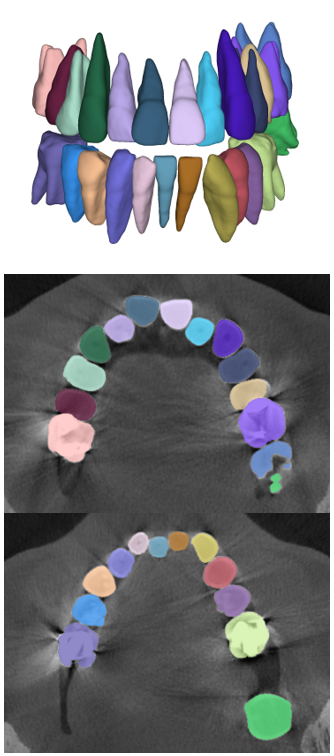

Digitized orthodontic applications in dentistry have increased based on the development of cone beam computed tomography (CBCT) imaging. CBCT is a widely used medical imaging technique that provides high resolution 3D volumetric data. To build an effective computer-aided diagnosis system in orthodontic applications, such as oral treatment planning for tooth reformation and implant guide simulation, automatic segmentation of individual teeth from the CBCT images is an essential prerequisite (Fig. 1). However, accurate segmentation of an individual tooth from a CBCT image is a challenging task owing to heterogeneous intensity distribution, unclear boundaries between the tooth root and alveolar bone (Fig. 2a), and diverse shapes and poses. Moreover, the majority of CBCT images contain severe metal artifacts that hinder the accurate segmentation of teeth (Fig. 2b). In this study, we propose a fully automated instance segmentation framework using 3D images of teeth that is robust to several challenging conditions of the teeth, such as, dynamic poses, missing teeth, inter-tooth proximity, and presence of severe metal artifacts.

In this study, we propose a fully automatic, hierarchical method that performs accurate individual tooth detection followed by a CNN based on single pixel-wise labeling to segment the tooth (Fig. 3). We first extracted the volume-of-interest (VOI) region by pose regression using neural networks. Then, the extracted VOI region was realigned based on the pose (i.e., axes). Subsequently, we detected individual teeth and performed individual tooth segmentation. The key components of our method are the accurate tooth detection framework through VOI realignment, which reduces the inter-overlapping area between boxes, multiclass classification within a detector, which boosts the accuracy of metal-tooth detection, and the metal-robust CNN for accurate tooth segmentation.